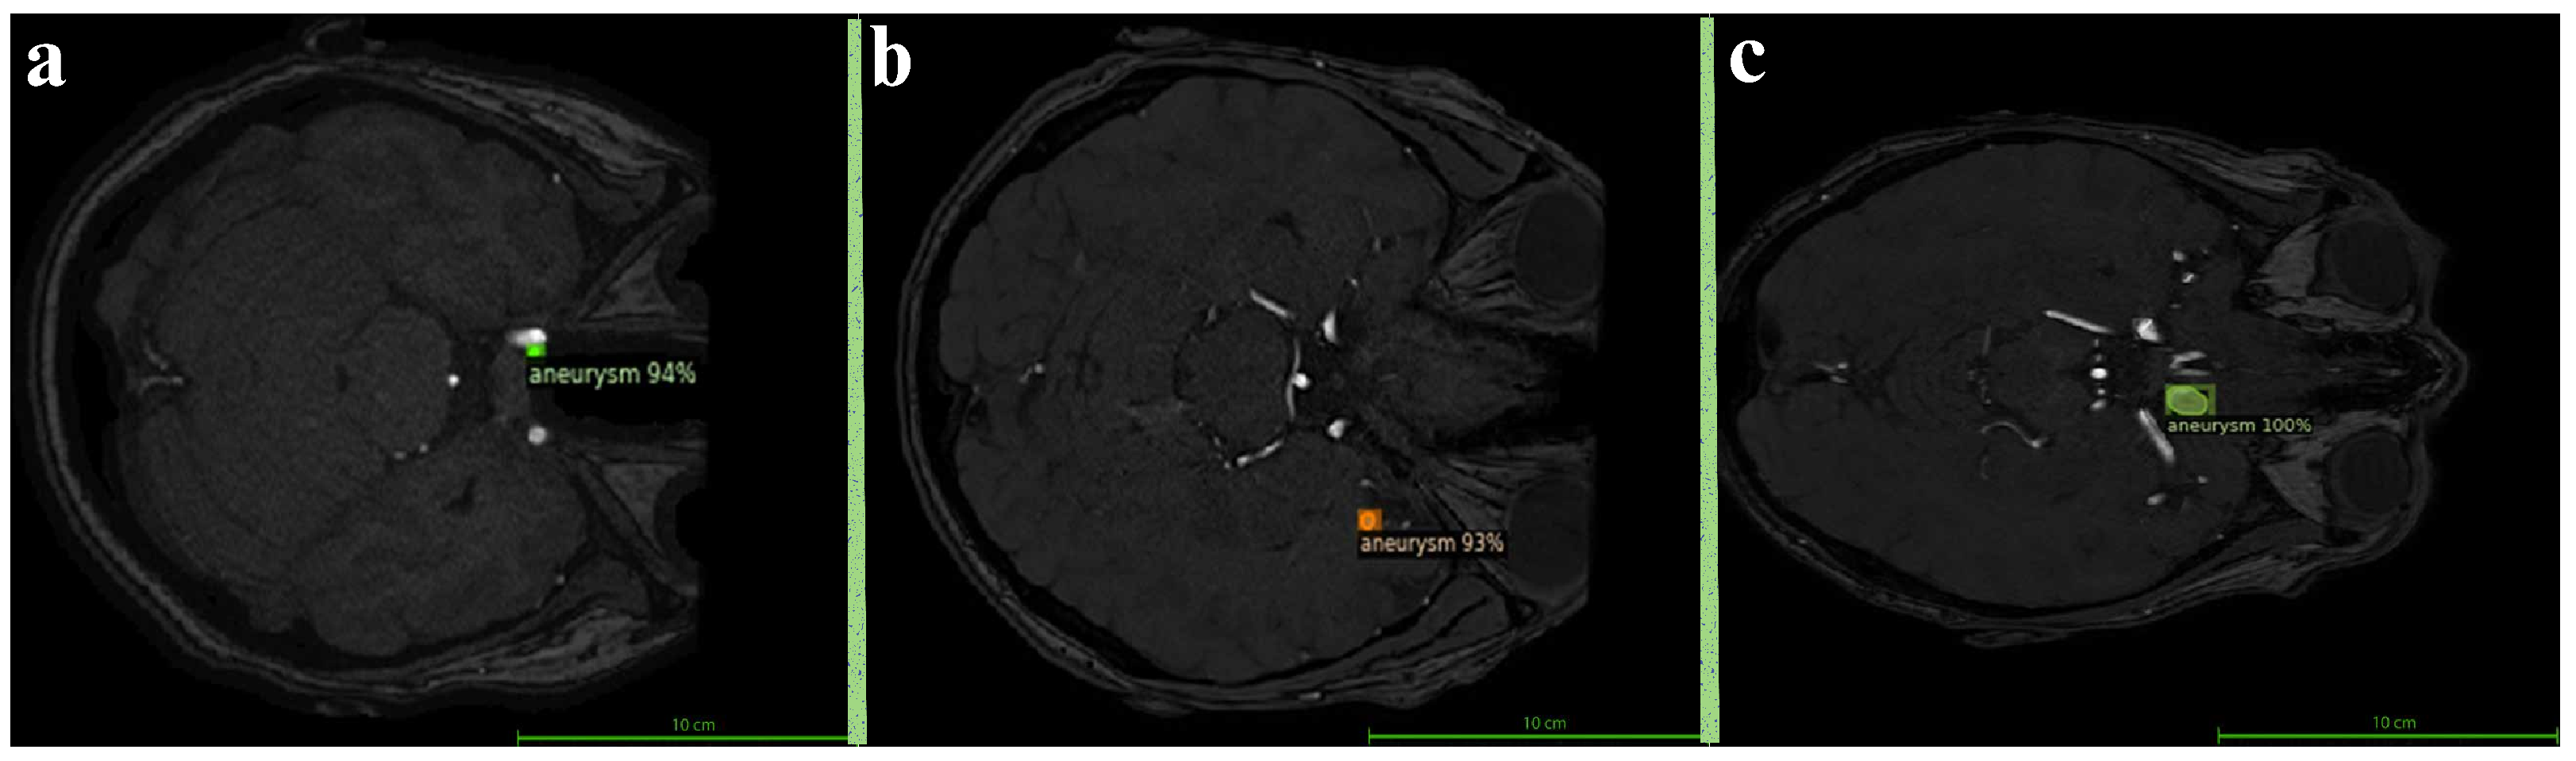

3.2. Performance by Aneurysm Size

Figure 5 summarizes the Dice, precision, and recall scores for each size category for visualizing the variation in performance across aneurysm sizes. This comparison highlights the model’s robustness in detecting larger aneurysms while also pointing to areas for improvement, particularly in enhancing recall for smaller lesions. In order to better illustrate the model’s detection performance, Figure 6 presents representative segmentation results for small, medium, and large aneurysms. These qualitative examples demonstrate the ability of the model to recognize diverse morphological patterns—from subtle, low-intensity lesions to large, well-defined aneurysmal regions. A more detailed quantitative evaluation across different aneurysm sizes is provided in Table 3. The model achieved the highest Dice score for large aneurysms (86.67%), followed by medium (74.05%) and small aneurysms (68.57%). Notably, the model maintained high precision for small aneurysms (92.31%), suggesting strong discrimination capability and a low false-positive rate in these challenging cases. However, the relatively lower recall (54.55%) indicates difficulty in consistently capturing small aneurysms, which is a known limitation in the literature due to their low contrast and subtle appearance.

Figure 6. Sample model predictions based on aneurysm size. (a) Small aneurysm with 94% confidence (b) Medium aneurysm with 93% confidence (c) Large aneurysm with 100% confidence.